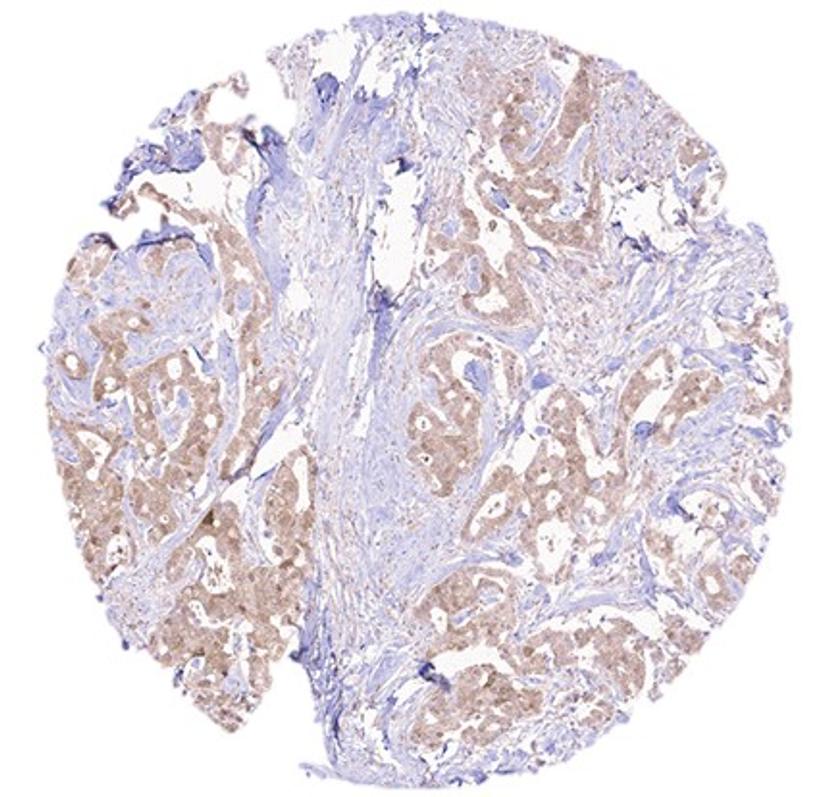

AMSBIO has supplied a custom monoclonal antibody (mAB) to researchers at the TU Dortmund in Germany to unravel the role of EDI3 in breast cancer development, its regulation by HER2 signaling, and its potential as a therapeutic target.

The team of researchers, led by Dr. Rosemarie Marchan, has conducted an extensive study to explore the clinical relevance of EDI3 - a glycerophosphodiesterase enzyme involved in choline metabolism, in HER2 + breast cancer, using the custom mAB against EID3 prepared and supplied by AMSBIO.

Dr Marchan commented, “We have tested many off-the-shelf antibodies over the years, with little to no success. We have also contracted companies to create a custom antibody for us, but again with limited success. Therefore, we are very thankful that a few years ago, we were able to get a great antibody against EID3 from AMSBIO. Using this precious antibody our team has been able to demonstrate that inhibiting EDI3 in ER-HER2+ breast cancer cells resistant to HER2-targeted therapy reduces viability and tumor growth”.